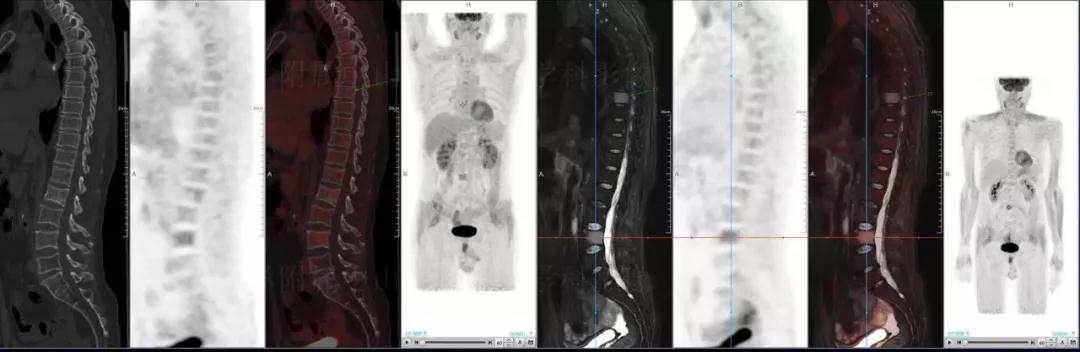

多發(fā)性骨髓瘤

中山醫(yī)院核醫(yī)學科基于聯(lián)影“時空一體”超清TOF PET/MR的融合顯像優(yōu)勢,進行了大量的臨床掃描,發(fā)現多例由MGUS向多發(fā)性骨髓瘤轉變,并從中總結出了一定的共同征象,未來可能實現多發(fā)性骨髓瘤的早期篩查。此外,PET/MR在多發(fā)性骨髓瘤的療效評估方面,也存在顯著優(yōu)勢。

(男性,53歲。確診多發(fā)性骨髓瘤10月。經過7周期VCD方案化療后,現行療效評價。)